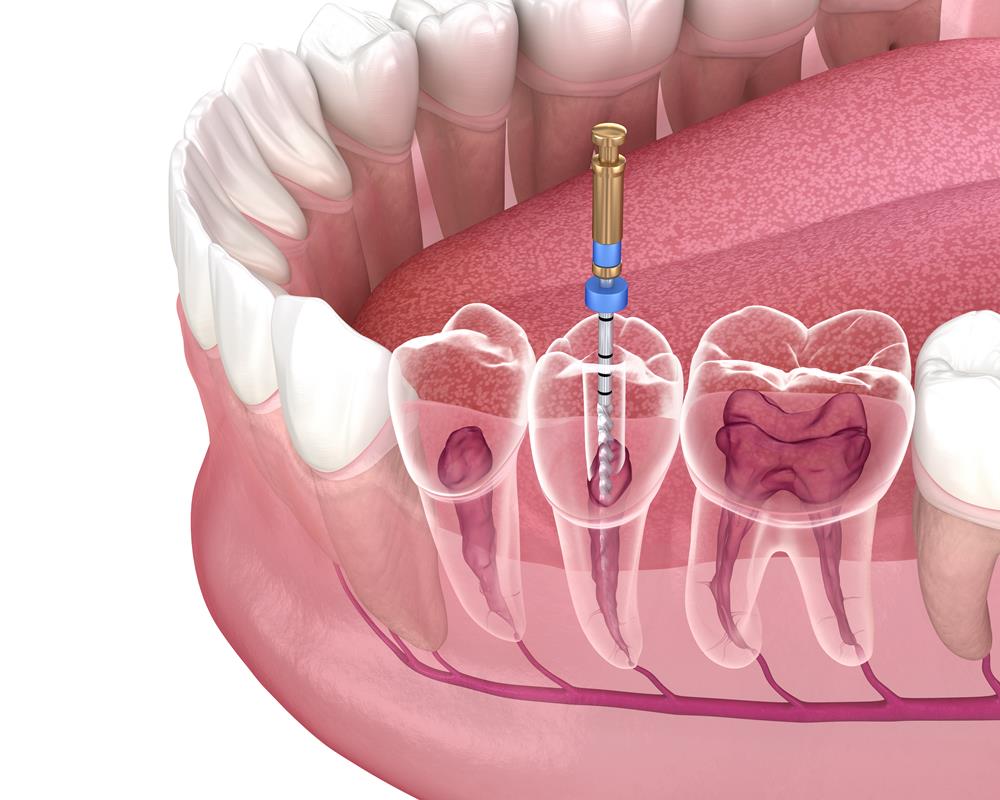

Our teeth consist of three major layers: the enamel, dentin, and central root canal cavity. The root canal houses the dental pulp, which comprises the blood vessels and nerves responsible for the nourishment and sensation of the tooth. When the oral bacteria gain entry to the root canal cavity, they can infect the pulp and cause a root canal infection.

Root canal therapy is often regarded as the last resort to save a severely infected tooth. The dentist will diagnose your condition thoroughly and determine your candidacy for the procedure. If the severity of the infection is mild, it can be treated using medication and restoration. But, if the infection has encroached on the pulp to a large extent, we will have to perform the therapy.

We will clean and disinfect the tooth and administer local anesthesia before commencing. A small hole will be made in the tooth, and the infected pulp will be removed through it using dental files of varying sizes. We will also scrub the walls of the cavity and remove the microbial debris using a jet of water. We will place a small amount of antibiotic medication in the cavity before sealing it off using filling material to prevent reinfection. Since the tooth could weaken gradually due to the absence of nourishment, we will restore it using a ceramic dental crown to hold it intact and prevent damage.